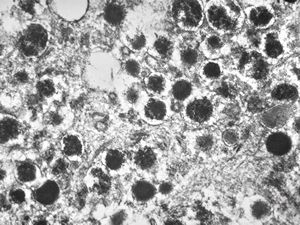

F,68y. | APUD carcinoma

F,68y. | APUD carcinoma

F,68y. | APUD carcinoma

F,68y. | APUD carcinoma

F,68y. | APUD carcinoma (Bodian siver impregnation)